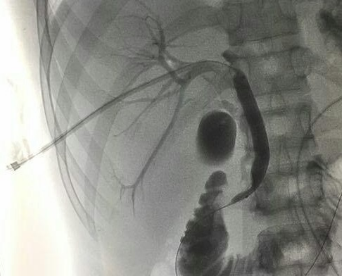

作為一種治療手段,主要是通過經(jīng)皮肝穿刺導(dǎo)入導(dǎo)絲,引流管, 膽道支架, 球囊等設(shè)備對(duì)肝膿腫,膽結(jié)石,阻塞性黃疸,膽道狹窄進(jìn)行后續(xù)治療。

肝穿刺操作可通過一步法和二步法實(shí)現(xiàn),我們提倡二步法操作即先用細(xì)針穿刺,特別是通過肝穿刺建立通路處理膽道病變時(shí),待穿刺成功后,先導(dǎo)入細(xì)導(dǎo)絲,再逐步引入導(dǎo)入鞘管和0.038英寸的粗導(dǎo)絲。另外在進(jìn)行手術(shù)前的1~2天,需做好充分的準(zhǔn)備,患者需要進(jìn)行一些常規(guī)肝臟的生化檢查以及凝血功能的檢測(cè),還要進(jìn)行血常規(guī)和血小板的檢測(cè),在手術(shù)前的一天要用超聲來定位穿刺點(diǎn),了解穿刺點(diǎn)的周圍有沒有比較大的血管或者是腫大的膽囊。在進(jìn)行肝穿刺以后需要住院休息幾天。